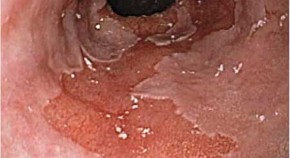

This Review considers the endoscopic ablative techniques now available for use in the esophagus—photodynamic therapy, laser therapy, multi-polar electro-coagulation, argon plasma coagulation, endoscopic mucosal resection, radiofrequency ablation and cryotherapy. At present, photodynamic therapy is the only FDA-approved ablative modality for high-grade dysplasia in Barrett's esophagus, but, at this stage, it is not clear which technique will emerge as superior for the treatment of esophageal adencocarcinoma precursors.